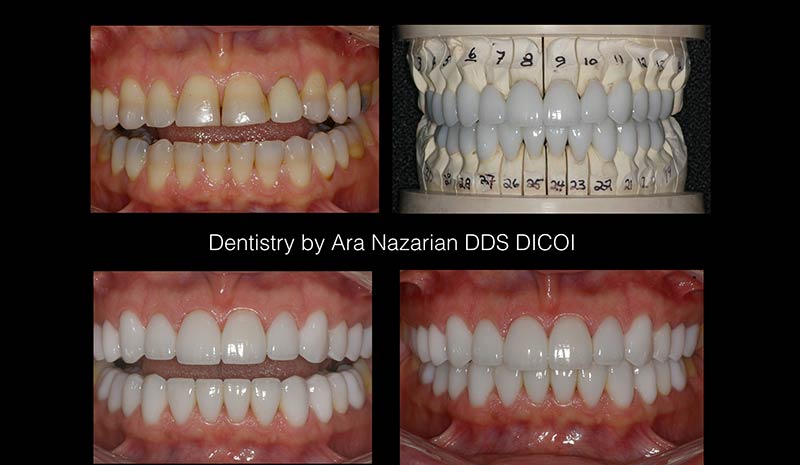

Porcelain Veneers Makeover

Dr. Nazarian may recommend porcelain veneers to restore teeth with chips, cracks, stains, or other minor imperfections. He can also use veneers to improve the appearance of misshapen teeth.

Crown Makeover

Dental crowns are used in smile makeovers to cover teeth that are:

Cosmetic and Reconstructive Case History Example

Since this patient was born and raised in a foreign country, she didn’t have access to orthodontic treatment. A history of treating common childhood illnesses also caused the dark bands of staining on almost all of her teeth (severe tetracycline stains).

During routine occlusal studies and analysis, Dr. Nazarian determined that certain orthodontic treatments could be provided on an accelerated schedule that would fix the orthodontic abnormalities of an adult underbite, combined with treatments to address a minor crossbite condition.

Due to the mismatched pairings of upper and lower teeth in several areas of her jaw, the patient soon understood that, while some tooth structures would respond well and endure with custom veneer laminates, there were several other tooth relationships that would destroy a veneer application because of the biting characteristics of each upper and lower tooth pair.

Biting surface realignment can be achieved through traditional orthodontics (long term), orthognathic surgery (costly and time-consuming), and custom fabrication of dental components (crowns) that effectively reconfigure and shift the occlusal surfaces.

The repositioned lower teeth were then fitted with either veneers or custom crowns to optimize the positioning of biting surfaces between the upper and lower jaw.

Cosmetic and Reconstructive Drama

The combination of short-term orthodontic straightening and bite opening moved the jaw into the position that Mother Nature failed to produce. Lastly, Dr. Nazarian’s choices of veneers and porcelain crowns on different tooth structures assure that occlusion-caused breakage will not occur.